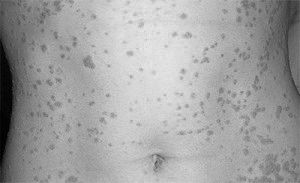

Звичайний або вульгарний псоріаз у дітей

Псоріаз у дітей супроводжується свербінням, який доставляє їм великий дискомфорт. Через постійне свербіння утворюється безліч расчесов, що може стати причиною приєднання вторинної інфекції. Ділянки шкіри, покриті псоріатичні бляшки, що мають тенденцію до злиття, мають характерний вигляд і називаються «парафінові озера».

псоріаз каплевідний